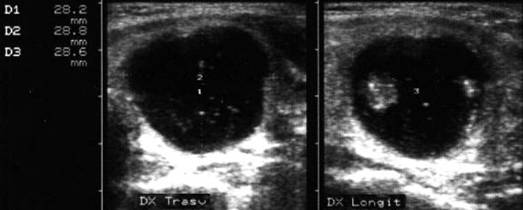

Lob drept , proiectie trasversala si longitudinala.

Femeie 19 ani. Leziune marcant hipoecogen cu intarire posterioara, de 16x20x26mm (4 cc) in lobul drept.

Examen citologic: macrofagi, fara tireocite.